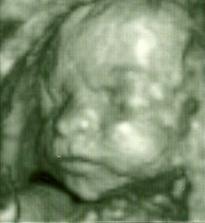

Naše druhé :o)

51 mm od hlavicky po zadok :o) a ty??